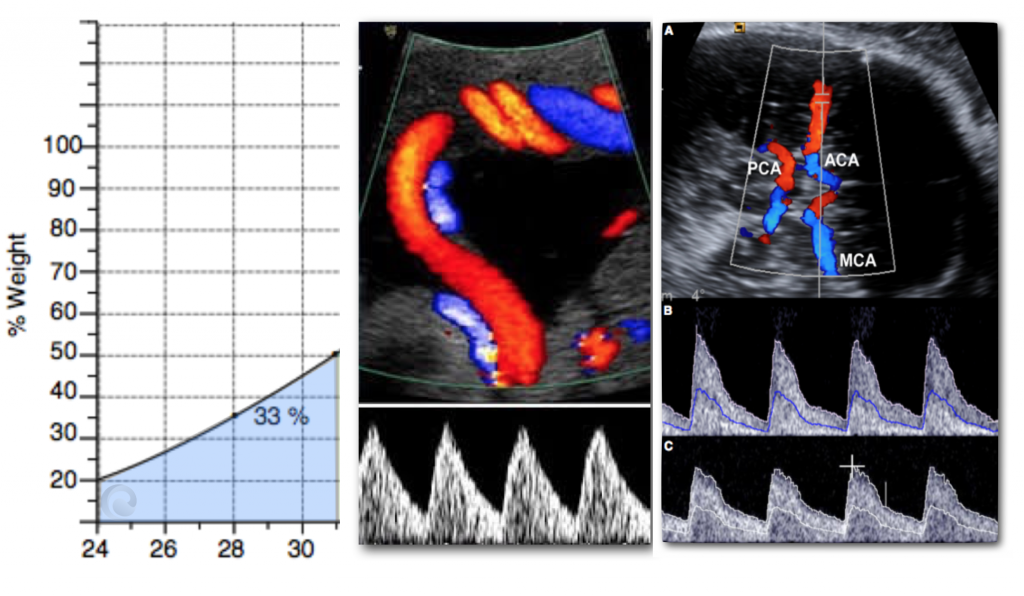

Además de medir al bebé (biometría), evaluaremos la fisiología fetoplacentaria verificando tres parámetros de bienestar: el flujo sanguíneo en el cordón umbilical y el cerebro (y eventualmente en algunos otros vasos fetales), el volumen de líquido amniótico y los movimientos fetales.

En la mayoría de las embarazadas no hace falta hacer más ecografías después de las 32 semanas. Sin embargo, 1 de cada 20 mujeres experimentará disfunción placentaria tardía que puede manifestarse como preeclampsia o disminución del crecimiento fetal en el tercer trimestre tardío. La medición del flujo en las arterias uterinas nos permite identificar a la mayor parte de estas pacientes y ofrecerles una ecografía adicional a las 36 semanas.

1. Doppler umbilical